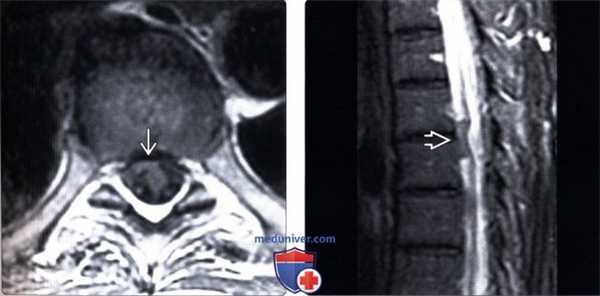

(Слева) Т1-ВИ, аксиальная проекция: деформация и вентральное смещение спинного мозга. Во время операции у данного пациента, у которого наблюдался прогрессирующий нижний парапарез, было подтверждено наличие дефекта дурального мешка.

(Справа) Т2-ВИ, сагиттальная проекция: фокальная деформация и вентральное смещение спинного мозга, достигающего задней поверхности тела позвонка. Дифференциальный диагноз включает заднюю арахноидальную кисту и грыжу спинного мозга.